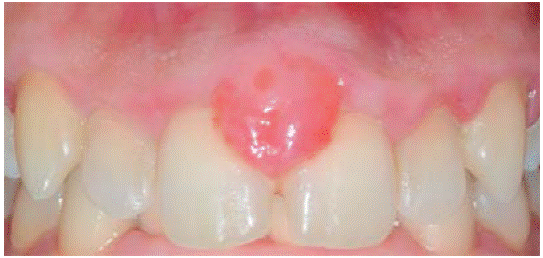

Controles: después de una semana se observó reducción del volumen de la lesión, sin embargo, persistía la coloración rojiza en la zona, por lo cual se mantuvo en observación. Después de seis meses presenta recurréncia de menor intensidad (7x7 mm) (Figura 15). Además se observa presencia de placa obteniéndose un índice de higiene oral (O'Leary) del 52%. Se realiza nuevamente una sesión de instrucción de higiene oral, remoción de placa y por segunda vez la escisión de la lesión. En esta intervención se eliminó mayor margen de tejido aparentemente sano, llegando a remover el periostio adyacente a la lesión.

Durante los siguientes controles la evolución fue favorable, manteniendo mejores niveles de higiene oral y sin presentar recurréncia de la lesión hasta un periodo de seguimiento de siete meses (Figura 16).